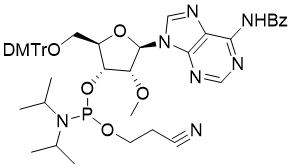

馬鞍山致研生物醫(yī)藥科技有限公司成立于馬鞍山市鄭浦港新區(qū)現(xiàn)代產(chǎn)業(yè)園。公司專(zhuān)注于生物小分子、醫(yī)藥中間體相關(guān)產(chǎn)品的研發(fā)和生產(chǎn),產(chǎn)品主要包括DNA亞磷酰胺單體、RNA亞磷酰胺單體、特殊單體以及按照客戶(hù)要求定制的RNA和DNA,并且公司提供定制合成等方面的研究服...

馬鞍山致研生物醫(yī)藥科技有限公司成立于馬鞍山市鄭浦港新區(qū)現(xiàn)代產(chǎn)業(yè)園。公司專(zhuān)注于生物小分子、醫(yī)藥中間體相關(guān)產(chǎn)品的研發(fā)和生產(chǎn),產(chǎn)品主要包括DNA亞磷酰胺單體、RNA亞磷酰胺單體、特殊單體以及按照客戶(hù)要求定制的RNA和DNA,并且公司提供定制合成等方面的研究服...